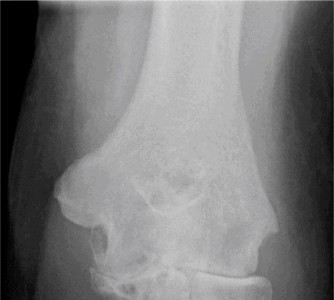

Treat a patient with infected total shoulder arthroplasty? CASE 21 A 70-year-old, right-hand-dominant female presents to clinic complaining of 4 years of gradually worsening chronic right shoulder pain and stiffness. She says the pain is worse at night and with any range of motion, denies a history of trauma, pain in other extremities, or numbness or tingling of the right upper extremity. She notes that her mother suffered from rheumatoid arthritis that affected her shoulder. Physical examination reveals decreased muscle bulk over the right supra- and infraspinatus fossae compared to the contralateral side, limited active and passive ROM, marked weakness with external rotation, and 4+/5 strength with shoulder abduction. X-rays of the right shoulder are shown in Figures 2–58 and 2–59.

Figure 2–58

Figure 2–59

The correct answer is (C). Rotator cuff tear arthropathy consists of a combination of rotator cuff insufficiency, glenohumeral joint degenerative changes, and superior humeral head migration. It is more common in women and also more often found on the dominant side. The patient’s clinical examination with weakened external

rotation and muscle atrophy signaling incompetent supra- and infraspinatus muscles point to rotator cuff insufficiency, and her plain films reveal narrowed glenohumeral joint space as well as superior migration of the humeral head. Choice D is incorrect because, while radiographs would show narrowing of the glenohumeral joint space, they would also likely show numerous osteophytes and posterior wear of the glenoid. Choice B is incorrect because, while adhesive capsulitis does present as decreased active and passive range of motion, the patient’s constellation of symptoms pointing towards rotator cuff insufficiency along with the radiographs make cuff tear arthropathy the more likely choice. Finally, Choice A is incorrect because even though she has a positive family history of rheumatoid arthritis, it is less likely to present only in a single joint. Also, rheumatoid arthritis on radiography appears more as an erosive process without the characteristic superior migration of the humeral head.

The correct answer is (A). Superior migration of the humeral head would be most indicative of chronic rotator cuff insufficiency associated with cuff tear arthropathy, as it is a direct result of the inability of the rotator cuff tendons to help maintain the humerus in its normal position. Acetabularization of the undersurface of the acromion is commonly associated with superior migration of the humeral head found in rotator cuff tear arthropathy, and can be assessed using the Hamada classification, which is based on measurements of the acromiohumeral interval on radiography (Table 2–8). Choices B and C are incorrect because, while narrowed glenohumeral joint space and subchondral sclerosis are associated with rotator cuff arthropathy on radiographs, they indicate degenerative joint changes rather than chronic rotator cuff insufficiency. Choice D is incorrect because it is not a specific sign of rotator cuff arthropathy.